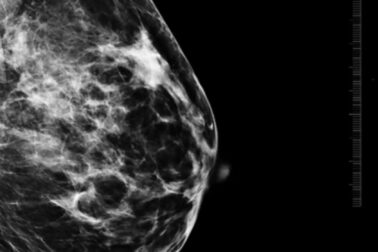

„Mikrokalcifikáty môžu byť v úplne skorom štádiu viditeľné len na mamografii, často ide o zmeny veľké len niekoľko milimetrov. Práve preto je mamografické vyšetrenie také dôležité a nenahraditeľné. Väčšie zmeny môžu byť neskôr viditeľné aj na ultrazvuku,“

vysvetľuje MUDr. Alexandra Bieliková, lekárka rádiológie AGEL Mammacentra sv. Agáty.

Lekári pri hodnotení mikrokalcifikátov sledujú viacero znakov, napríklad ich veľkosť, tvar, hustotu, rozloženie v prsníku či to, ako sa menia v čase. Práve tieto informácie pomáhajú určiť, či ide o bežný a neškodný nález, alebo o zmenu, ktorú treba podrobnejšie vyšetriť.